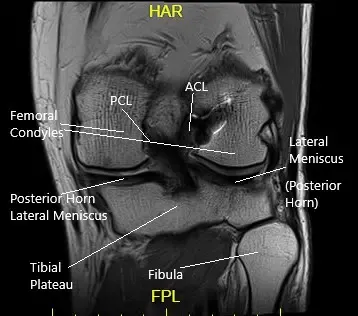

How the Body Part Normally Works? (Relevant Anatomy)

The knee joint is a hinge joint composed of the thigh bone (femur), shin bone (tibia), fibula, and kneecap (patella). The ligaments, cartilage, and menisci work together to provide stability and allow smooth movement.

- Articular cartilage cushions and protects the bones.

- Menisci serve as shock absorbers between the femur and tibia.

- Ligaments, including the ACL, PCL, MCL, and LCL, stabilize the knee by preventing excessive movement.

Ligaments

The ligaments of the knee along with the meniscus provide stability to the knee. Tears or rupture of the ligaments and menisci are the most common cause of knee buckling.

Anterior Cruciate Ligament (ACL)

The ACL runs from the front and middle of the tibia to the outer and backward side of the femur. The ligament provides stability mainly in the front and back of the knee. The ligament also stabilizes the rotatory movement of the knee.

Posterior Cruciate Ligament (PCL)

The PCL is present behind the knee joint. Along with ACL, it provides stability in the front and back of the knee. Similar to ACL, the PCL also provides rotational stability.

Medial & Lateral Collateral Ligaments

The medial collateral ligament provides stability on the inner side of the knee. Similarly, the lateral collateral ligament provides stability on the outer side of the knee.